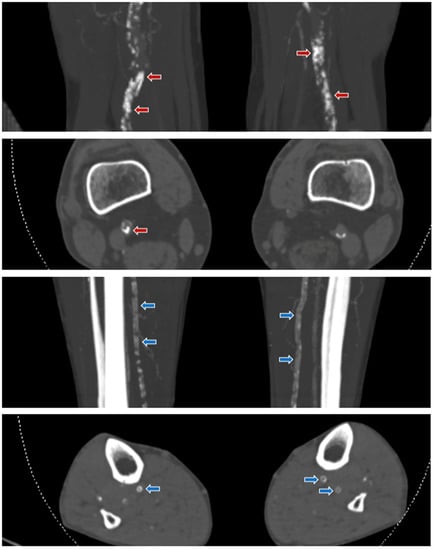

Figure 2.

Examples of different calcification patterns in patients with CLI. Shown are coronal MIP and axial 3 mm CT angiography images of the lower extremities. A. Top two figures: the red arrows in femoropopliteal arteries showing irregular/patchy, thick, and non-annular calcifications corresponding to a dominant intimal calcification pattern. B. Bottom two figures: the blue arrows in the crural arteries showing continuous, thin, and annular calcifications corresponding to a dominant medial calcification pattern.